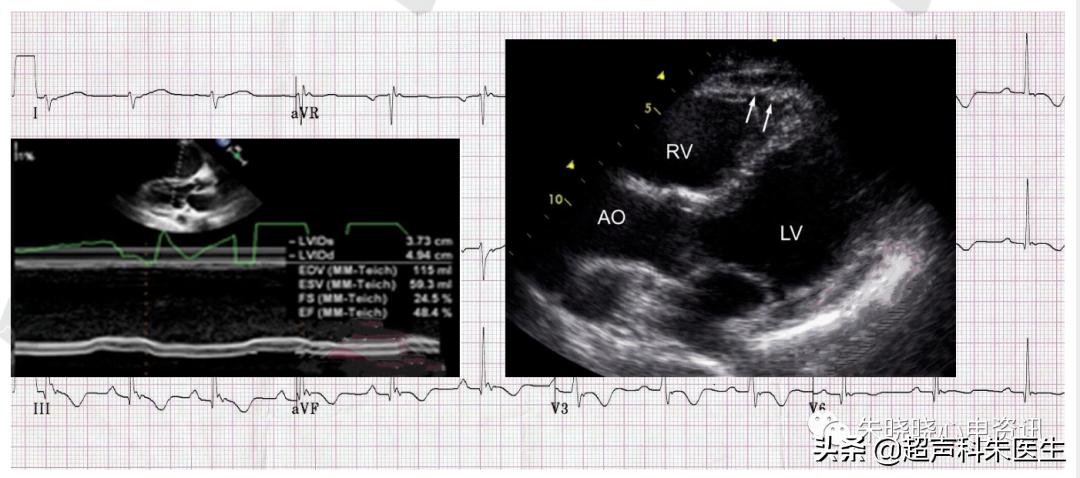

如图12为68岁男性,活动耐量进行性下降。心电图可见Epsilon波,右胸导联T波倒置;心脏彩超提示左室长轴切面右室壁菲薄,右室扩大,右室壁活动明显降低;患者的心肌活检示,病变心肌被脂肪细胞取代。

图12:V1导联可见Epsilon波

致心律失常性右室心肌病 (ARVC) ,可以使病变区心肌细胞延迟缓慢除极,造成室壁动作电位持续时间不一致,出现除极异常、复极障碍。

图13:ARVC患者的心脏彩超

ARVC特征性的心电图表现为Epsilon波。右胸导联T波倒置是ARVC常见的心电图表现,也是ARVC早期和敏感性指标之一 (48%~85% ARVC患者存在右胸导联的T波倒置) 。

图14:ARVC的病理特点